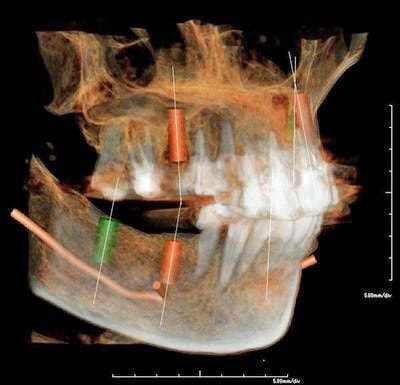

CTによる詳細な現状把握

レントゲンでは把握できないことまでCTでは確認することが出来ます。

身体を断面や立体図として見ることが出来、骨はもちろんの事、神経や血管に至るまで確認することができます。

そのデータを元に、どのような角度、どのような深さでインプラントを打ち込むかなど、的確な治療計画を立てることができます。

CT・診断:5,000円(税別)※インプラント治療を受ける場合は無料